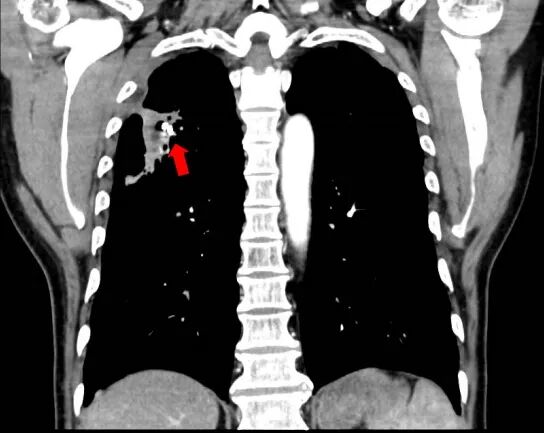

術(shù)前圖片:(紅色箭頭處為肺動(dòng)脈假性動(dòng)脈瘤)